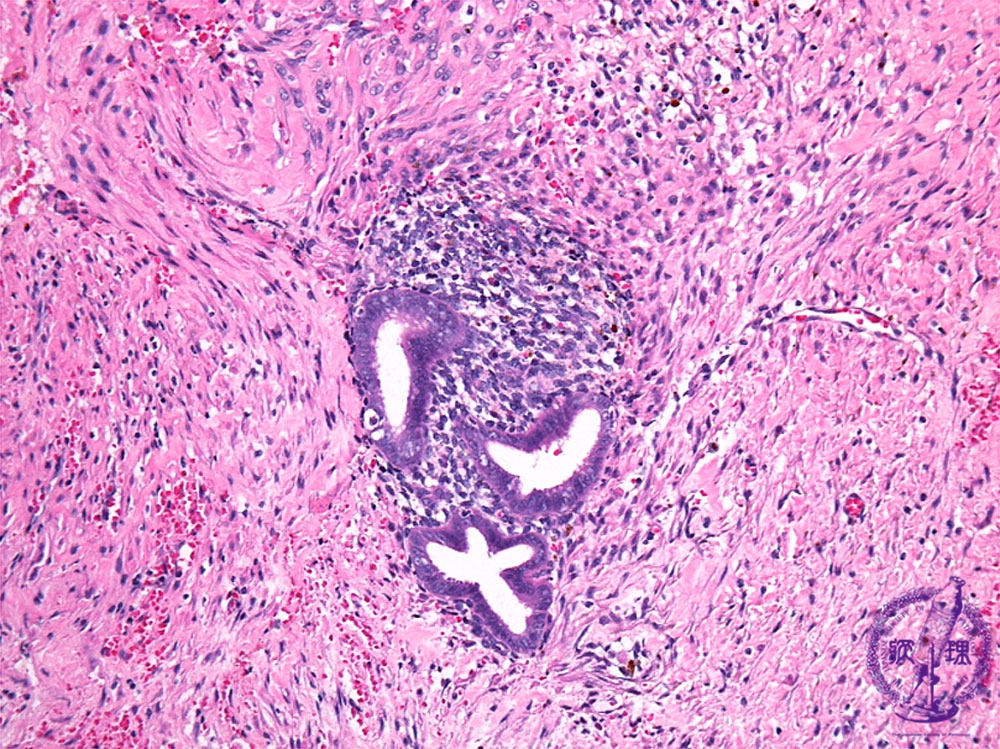

Histology (HE stain, intermediate power): Ectopic endometrial tissue in cyst wall.